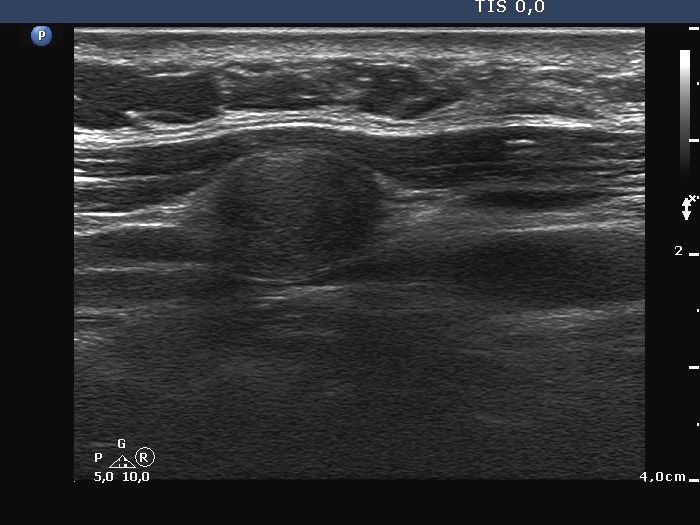

Ultrasonography: there was no parenchyma in the thyroid beds. Lateral to the right lobe there were several enlarged lymph nodes.

Cytological diagnosis: medullary carcinoma.